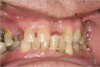

There are several ways to diagnose periodontitis. In addition to soft tissue evaluation, one of the most common and accurate methods is to use a periodontal probe in affected areas and record probing depths. Bleeding on probing is another indication of unhealthy periondontal tissues. Radiographs can be used, but they have limitations in initial diagnosis because bone loss is typically associated with severe and chronic periodontal disease; therefore, radiographs are better used to confirm diagnosis. However, vertical bitewings taken over time can be placed side-by-side to detect even slight differences in contrast.